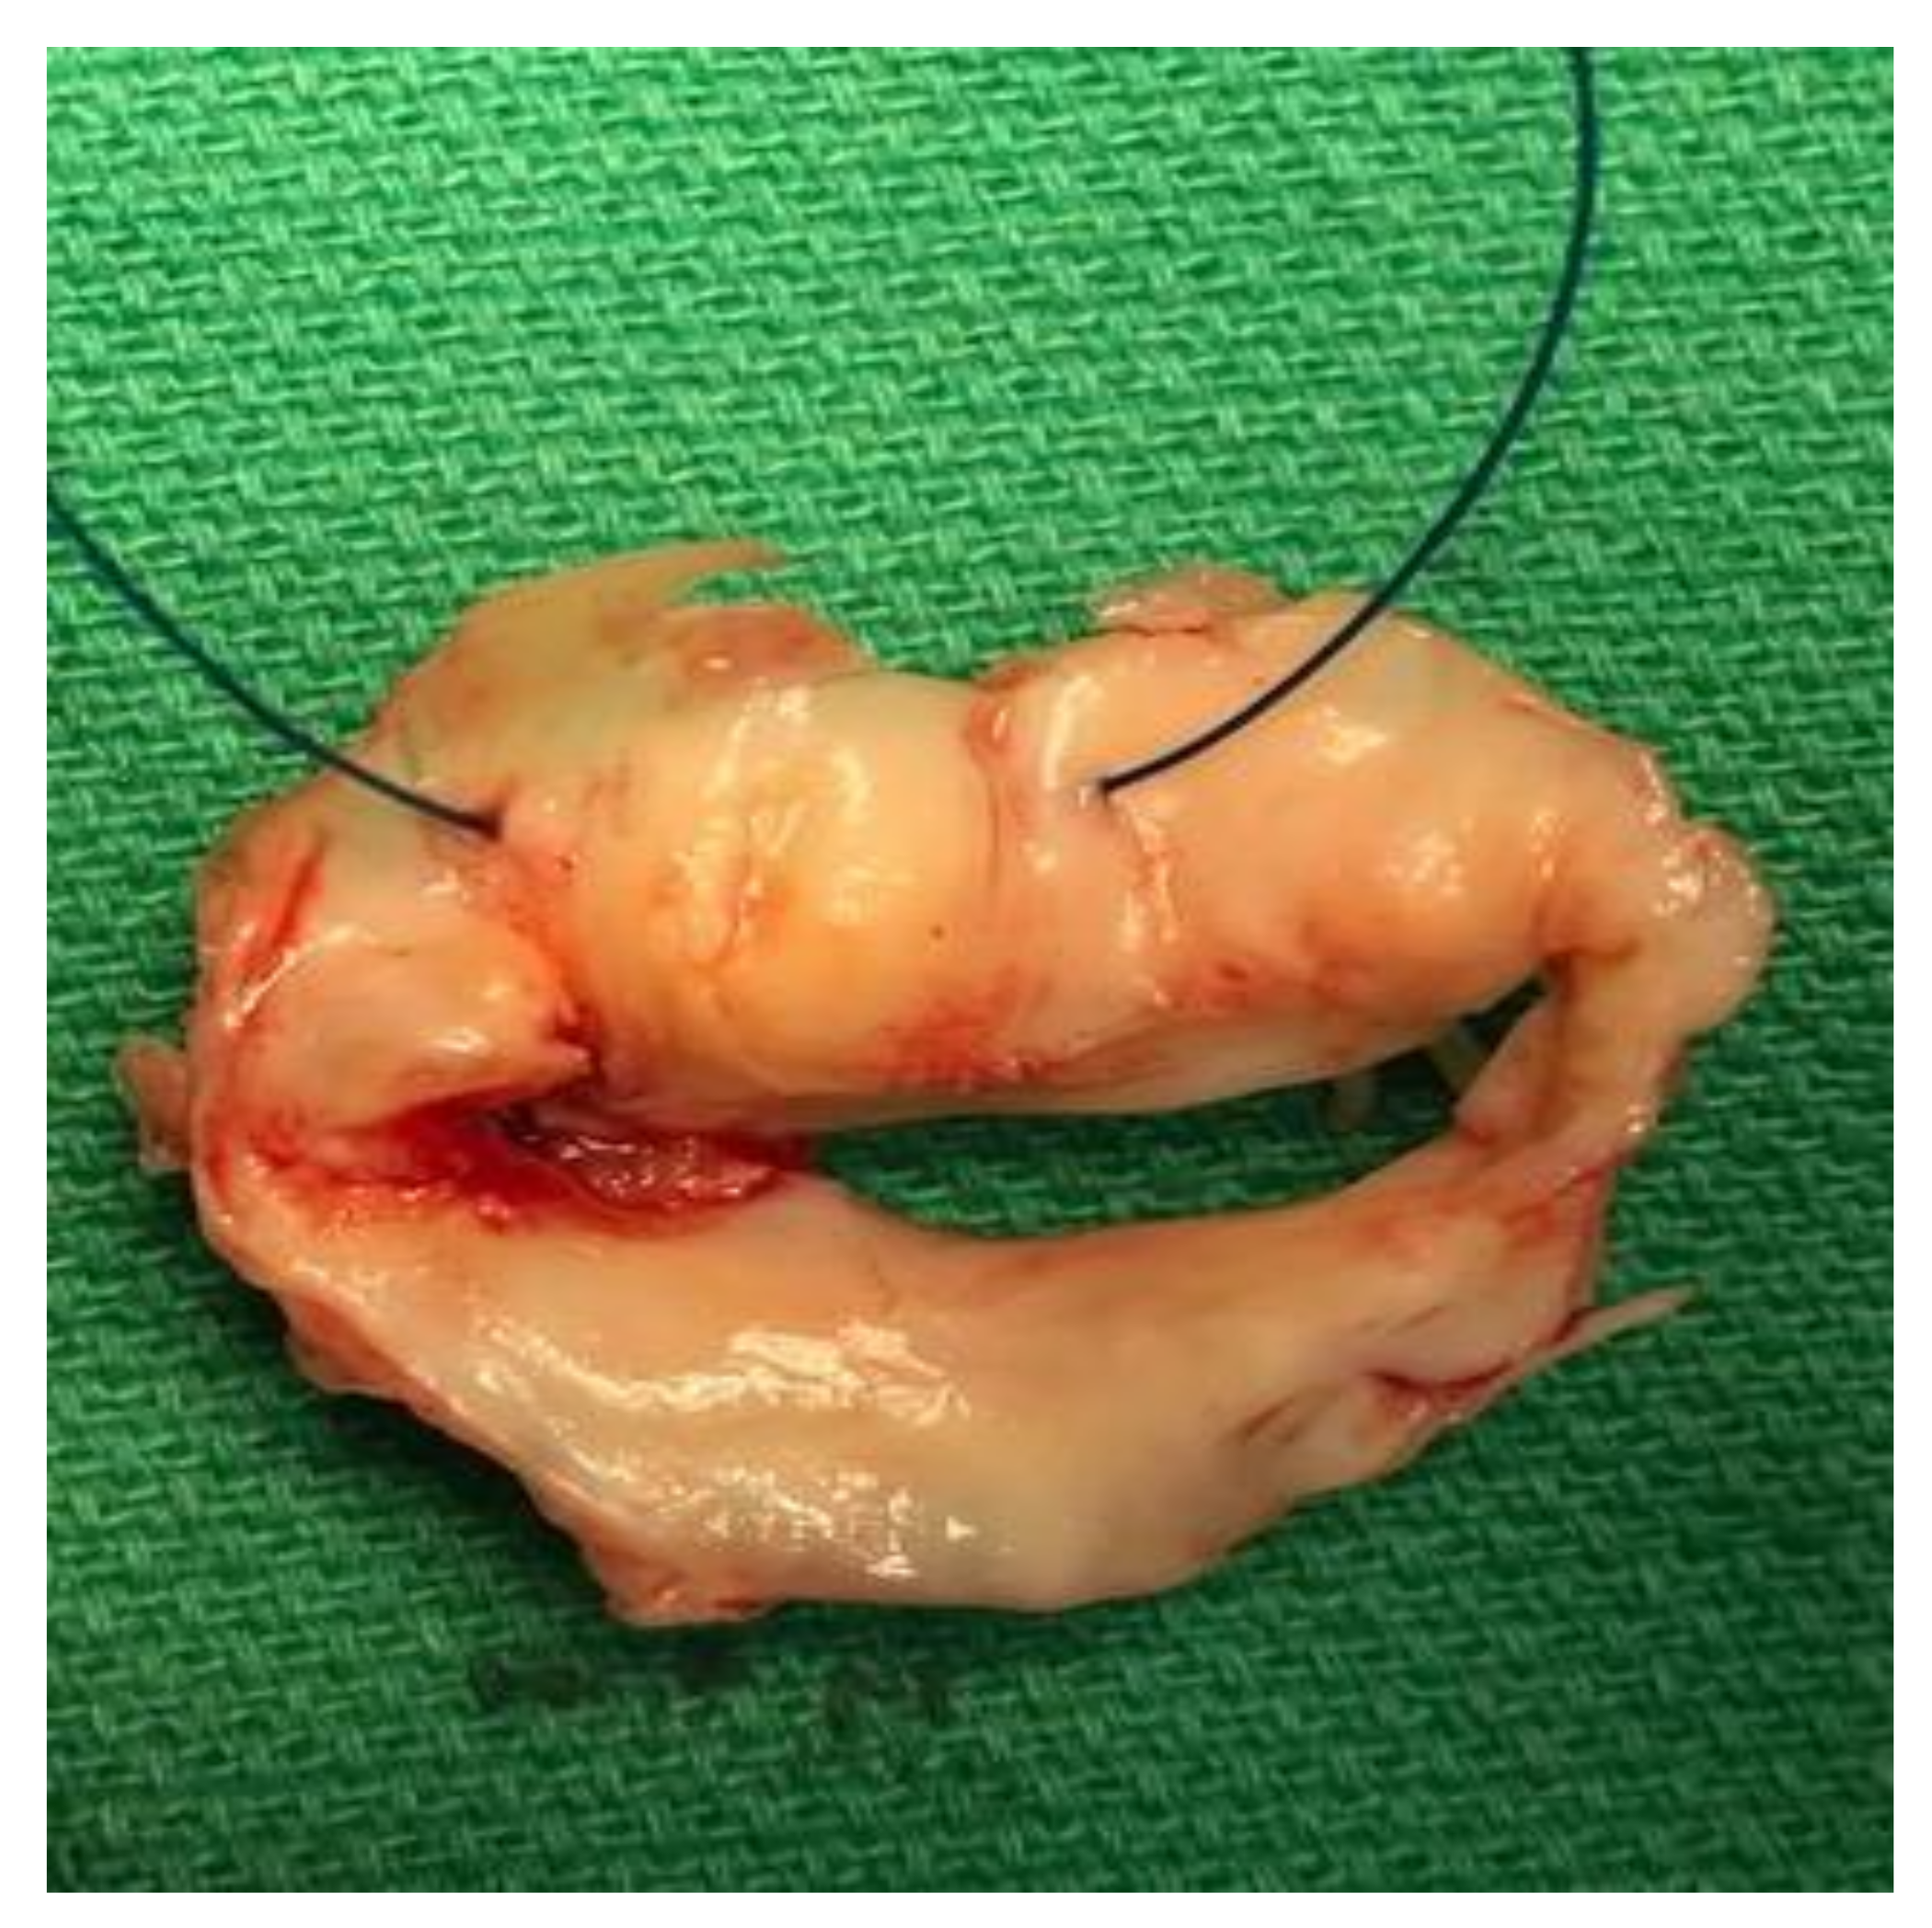

1. Case Report